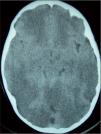

Caso 2. Niño de 2 años y 8 meses, con un cuadro de gastroenteritis de 48h de evolución que presentó dos episodios de crisis cerebrales generalizadas y fiebre elevada (40,4°C), con depresión neurológica brusca. Fue trasladado a nuestra UCIP; en el momento del ingreso presentaba una presión arterial de 80/40mmHg y relleno capilar de 3s, con una discreta anisocoria. En la TC craneal se observó un edema cerebral masivo (fig. 1), causante de una hipertensión intracraneal refractaria, que condujo a muerte encefálica en 24h.

La TC craneal proporciona una importante información acerca del pronóstico tanto en la fase aguda como en la convalecencia. La lesión aguda típica es el edema cerebral, que se asocia con un peor pronóstico a mayor gravedad de éste9, como ocurrió en nuestro segundo caso. A partir de los 7 días, se observan encefalomalacia y ventriculomegalia ex vacuo9.